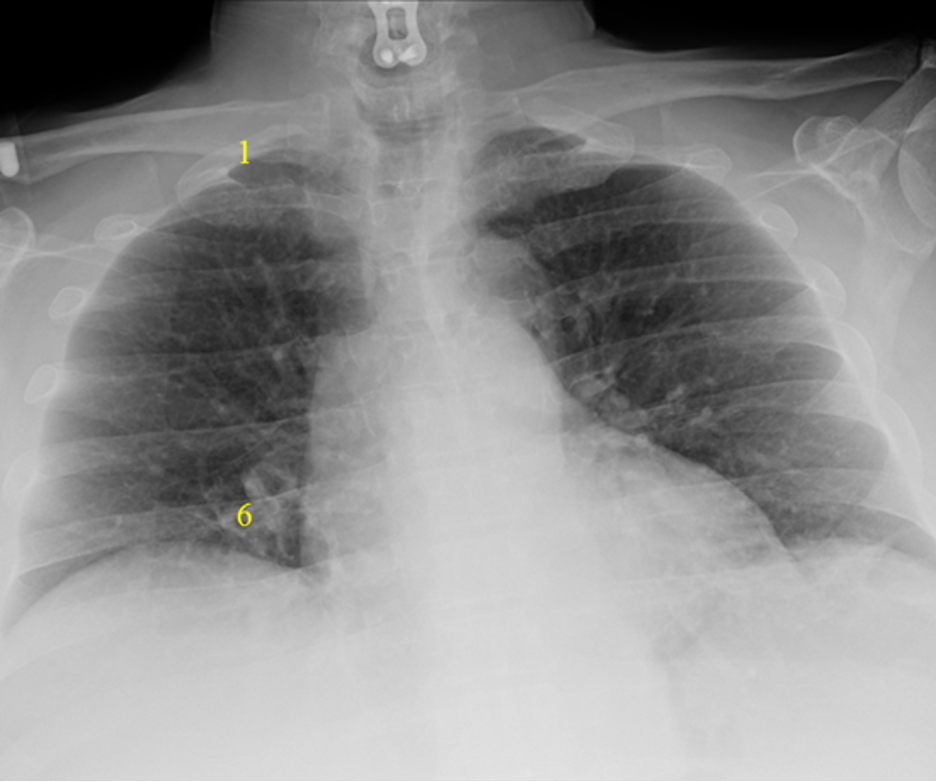

Rotation

It is not uncommon, especially for AP supine CXRs, for the patient to be slightly rotated. Rotation can be assessed by measuring the distance between the medial edges of the clavicles to the vertebral spinous processes. They should be equal or near equal. Anterior structures move the same direction as rotation so the clavicle/spinous process width is increased on the side to which the patient is rotated. This patient is rotated to the left.

Red Dotted Line = Slight Rotation to the Left

Here is a patient severely rotated to the left. Severe rotation can alter the normal cardiomedistinal contour and make interpretation difficult.

Significant Rotation to the Left